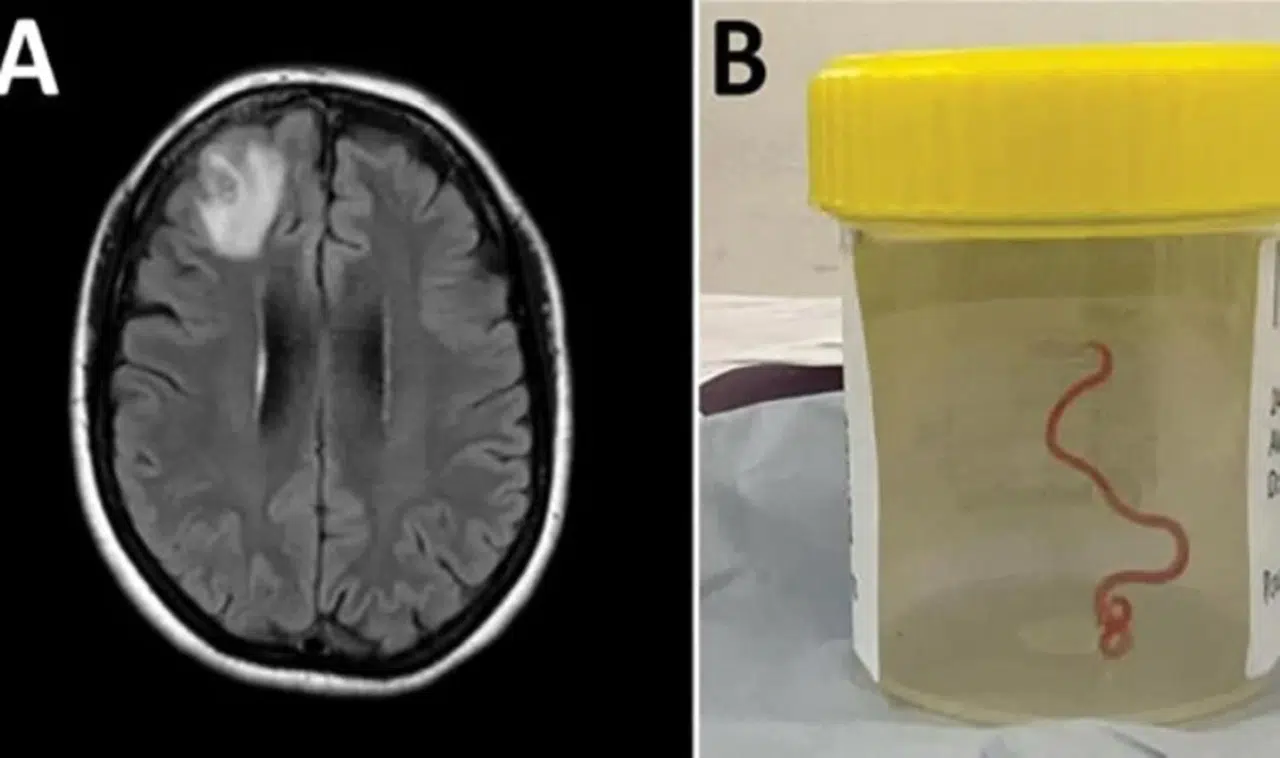

Avustralya Ulusal Üniversitesi’nden (ANU) yapılan açıklamaya göre 64 yaşındaki bir kadın karın ağrısı, ishal, kuru öksürük, ateş ve geceleri terleme şikayetleriyle ilk olarak Ocak 2021'in sonlarında hastaneye kaldırıldı. Daha sonra 2022 yılında unutkanlık ve depresyon şikayetleri de görülen kadın, Canberra Hastanesi'ne sevk edildi. MR taraması yapılan kadının, beyninin sağ ön lobunda anormallik tespit edilmesi üzerine ameliyat kararı verildi. Ameliyat sırasında doktorlar, kadının beyninde 8 santimetre uzunluğunda canlı solucan buldu. Latince adı "Ophidascaris robertsi" olan solucanın normalde piton yılanlarında bulunan bir parazit olduğu belirtildi. ANU ve Canberra Hastanesi'nin önde gelen bulaşıcı hastalık uzmanı Doçent Sanjaya Senanayake, “Bu, dünyada bir insanda görülen ile Ophidascaris vakasıdır” ifadesini kullandı.